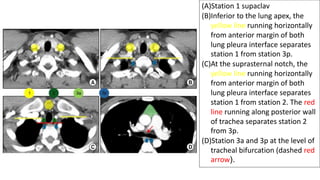

(A)Station 1 supaclav

(B)Inferior to the lung apex, the

yellow line running horizontally

from anterior margin of both

lung pleura interface separates

station 1 from station 3p.

(C)At the suprasternal notch, the

station 1 from station 2. The red

line running along posterior wall

of trachea separates station 2

from 3p.

(D)Station 3a and 3p at the level of

tracheal bifurcation (dashed red

arrow).